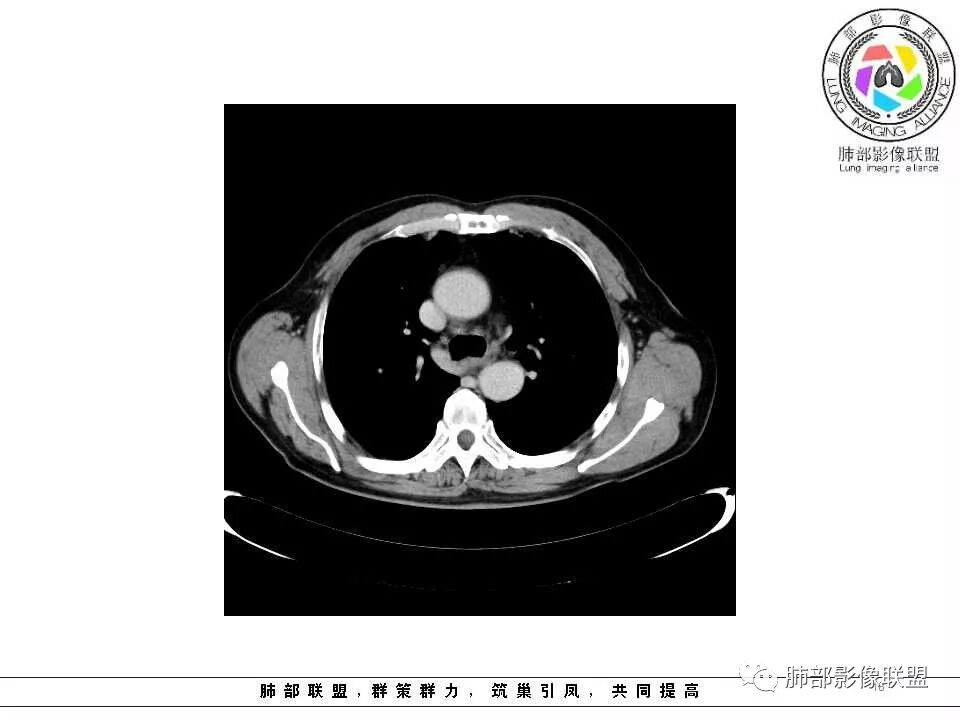

老年男性,两肺可见小叶中央型肺气肿,提示应该有抽烟史。2016年片,右肺门支气管稍模糊,考虑慢性感染,纵膈淋巴结稍大。但2017年左肺上叶新发占位,堵塞支气管,引起局部肺不张伴感染,且纵膈淋巴结较2016年变大,患者同时伴有咯血,考虑恶性。鳞癌?类癌?小细胞?

肺气肿背景,2016年左肺上叶上舌段见微结节,2017年5月左肺结节增大,密度均匀,边缘光滑锐利,与邻近血管关系密切,血管贴壁走行,外侧见尖状突起,下舌段片状影,沿着支气管走行,内有粘液栓,考虑鳞癌,鉴别小细胞肺癌。

老年男性,咯血1月,肺气肿背景,16年左肺上叶舌段结节,左肺门疑似淋巴结肿大,呈结节感。17年左肺上叶舌段见沿支气管走行分布结节 远端阻塞性肺炎,左肺门淋巴结肿大明显,首先考虑恶性病变,鳞癌?类癌?

老年男性,肺气肿背景,左肺上叶舌段一年前小结节后长大,实性,与邻近气管关系密切,远端有少许小片状炎症类小结节状,左肺门淋巴结肿大,首先考虑恶性,鳞癌可能性大,代排小细胞癌。病灶下方斑片状影,考虑炎症。

老年男性,肺气肿背景,对比前片,左肺上叶舌段结节较前进展,周围有斑片状条状密度增高影,左肺门淋巴结肿大,有咯血史抗炎后效果不佳,目测增强强化不好判断,考虑肺癌并阻塞性肺炎可能,鉴别炎症性肺癌,真菌类肺炎,肺脓肿,肺结核,建议完善肿瘤标志物,结核相关检查,病原体检查。

老年男性,咯血1月,肺气肿背景,左肺上叶舌段见沿支气管走行分布结节,呈葫芦样改变,左肺门淋巴结肿大明显,首先考虑恶性病变,小细胞癌可能